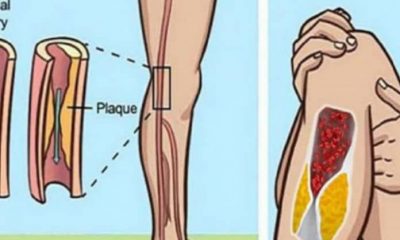

Φραγμένες αρτηρίες: 5 επικίνδυνα και προειδοποιητικά σημάδια. Τι να κάνετε για να θεραπευτείτε;

2 Απριλίου 2018Οι θρόμβοι του αίματος μπορούν να εμφανιστούν στις αρτηρίες ή τις φλέβες. Οι αρτηρίες μεταφέρουν οξυγονωμένο...